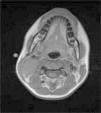

Niña de 13 años con tumoración cervical derecha detectada por la paciente desde hace unos 3 meses. A la palpación, bultoma de 3×4cm, de consistencia dura, adherido a planos profundos, sin inflamación ni dolor. No hay antecedente de proceso infeccioso, fiebre o síntomas constitucionales. La analítica sanguínea y la radiografía de tórax fueron normales. En la ecografía cervical se evidenció una masa en el espacio carotídeo derecho, de 4×2×4cm, de forma ovoidea, bien delimitada, isoecoica al músculo y con abundante vascularización en su interior. Estos hallazgos hicieron sospechar una tumoración de origen neural. Se completó el estudio con una resonancia magnética cervical. Las imágenes obtenidas (figs. 1 y 2) confirmaron como primera opción la sospecha de un schwannoma del vago, dada la morfología fusiforme de la lesión, con eje mayor longitudinal siguiendo el trayecto del nervio (fig. 3). Se realizó resección completa de la tumoración dependiente de la rama nerviosa cervical. El estudio histológico confirmó el diagnóstico de schwannoma del nervio vago. La paciente presentó síndrome de Horner derecho posquirúrgico sin otras complicaciones. Tras 6 meses no existe evidencia de recidiva tumoral.